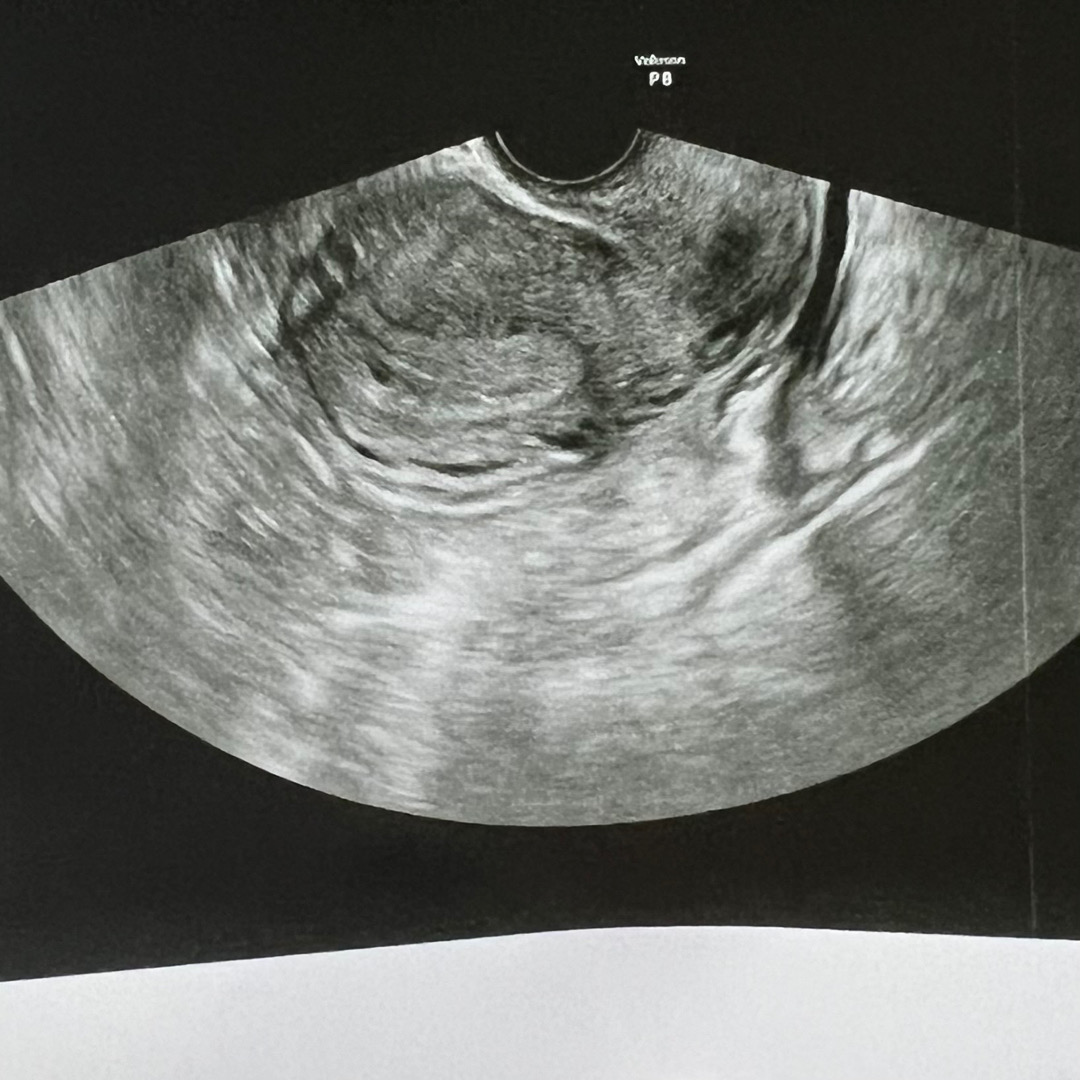

임신 4주

지금 4주차인데 다음주면 난황도 보일까요?

보통 5-6주차에 보여요. 저는 5주차아기집 6주차 난황봤오용 ^_^